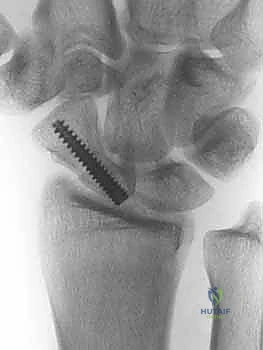

هذه هي المرحلة الحاسمة. يستخدم الدكتور هطيف أحدث التقنيات العالمية، وتحديداً "براغي الضغط بدون رأس" (Headless Compression Screws) مثل برغي هيربرت (Herbert Screw). يتم تمرير سلك توجيهي (K-wire) دقيق عبر الكسر لضمان الاستقامة، ثم يتم إدخال البرغي المجوف فوق السلك.

يقوم هذا البرغي المبتكر بضغط جزئي الكسر معاً بقوة شديدة، وبما أنه "بدون رأس"، فإنه يغوص بالكامل داخل العظم ولا يبرز ليحتك بغضاريف المفصل المحيطة.

6. الإغلاق والتأكيد الإشعاعي

أثناء الجراحة، يتم استخدام جهاز الأشعة السينية المتنقل (C-arm) للتأكد من الموضع المثالي للبرغي والاصطفاف التام للعظم. بعد التأكد، يتم خياطة الأنسجة والجلد بدقة تجميلية، ووضع جبيرة خفيفة.